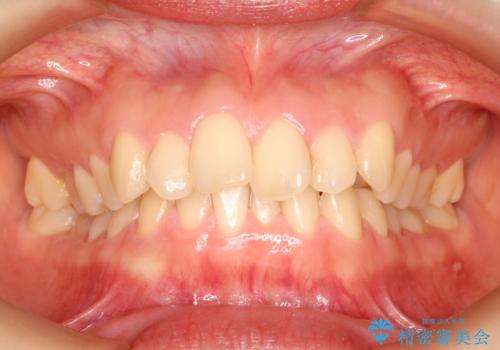

再矯正症例 前歯のガタガタと噛み合わせのズレをマウスピースで治した症例

コンプレックスだった前歯のガタガタがここまで綺麗になるなんて!!